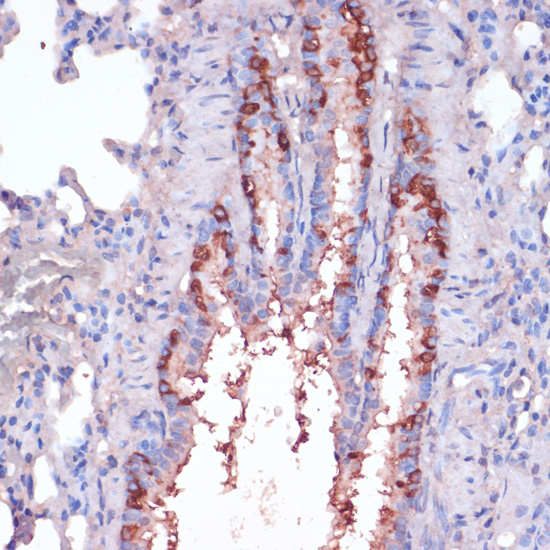

Immunohistochemistry of paraffin-embedded rat lung using RPL22 at dilution of 1:100 (40x lens).